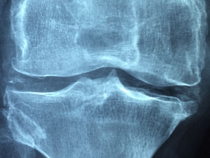

Spomedzi kovov boli v prvých pokusoch liečby zlomenín a ochorení kostí použité platina, železo, zlato či striebro. Zlato a platina boli svojou odolnosťou proti korózii veľmi žiaduce, ale ich cena bola vysoká a mechanická odolnosť slabá. Biokompatibilitu železa spochybnil výskyt ochorení, keď po implantácii dochádzalo… pokračuj